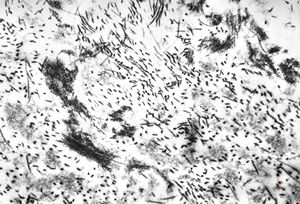

- 2. Infectious agents (viruses, bacteria, fungi, parasites)